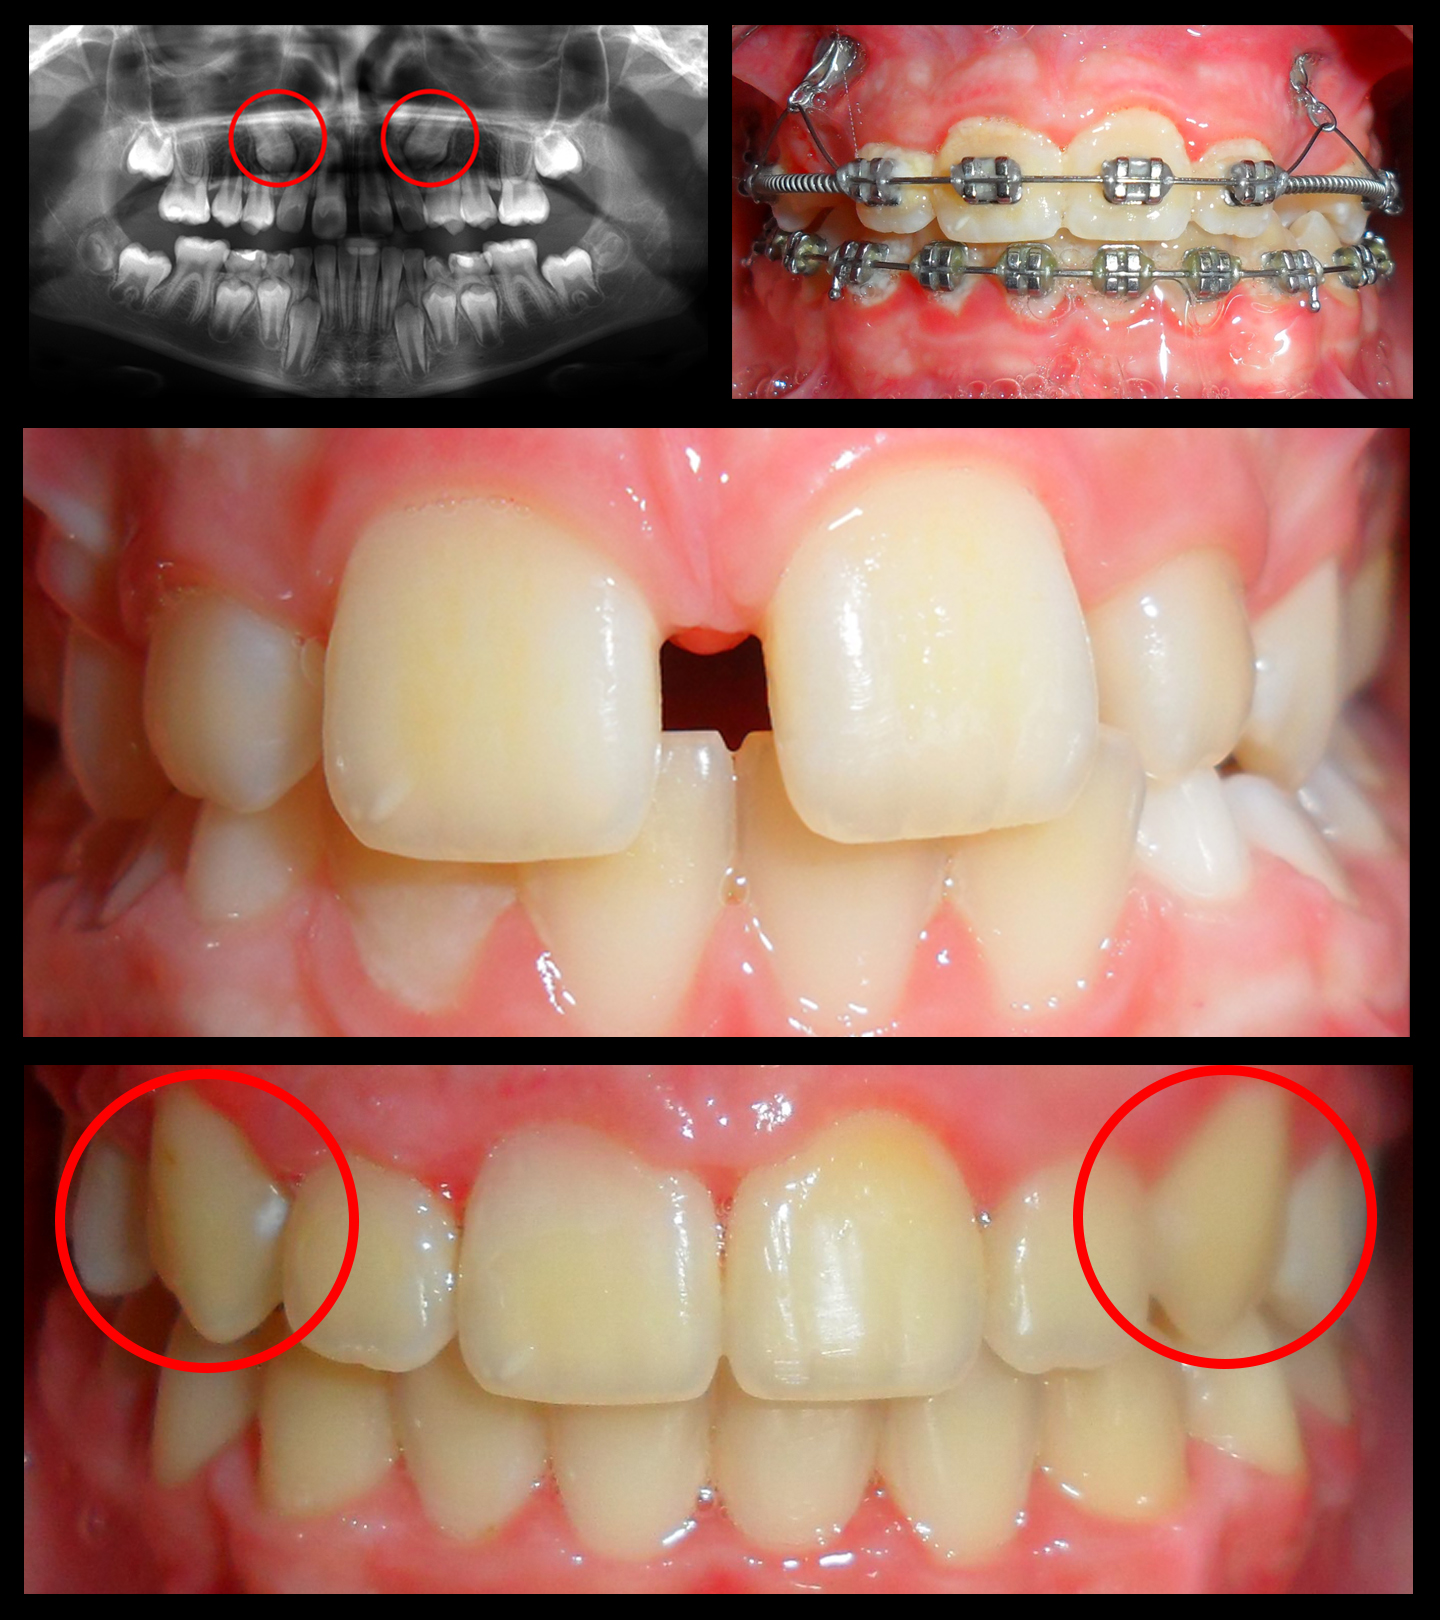

O našoj kvaliteti najbolje govore naši rezultati!

Centar za ortodonciju Petra Džapo